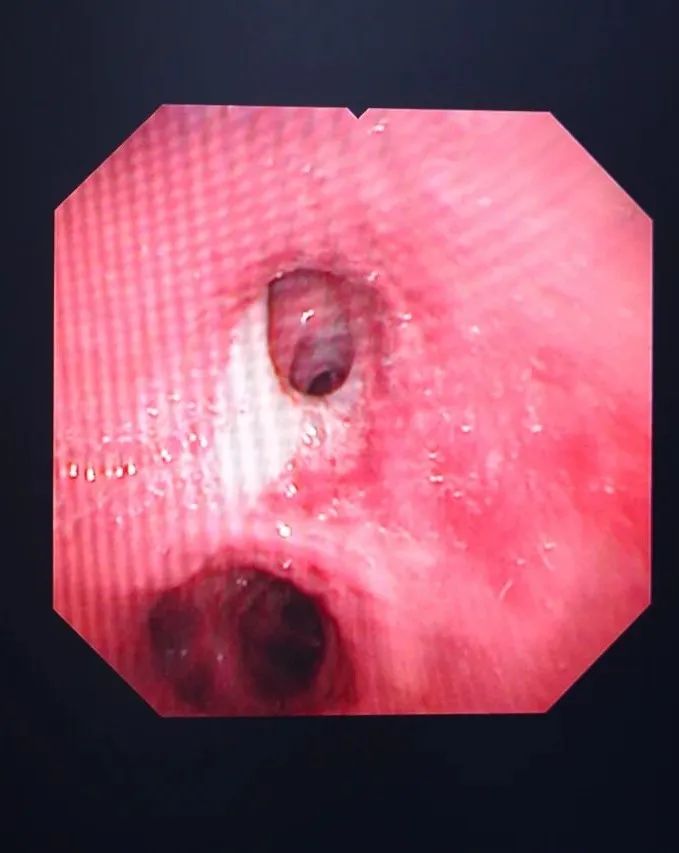

清理氣管分泌物

?支氣管鏡檢查就是將細(xì)長的支氣管鏡經(jīng)口或鼻置入患者的下呼吸道,醫(yī)生可以直觀地觀察到氣管和支氣管病變,并根據(jù)病變做出判斷。是呼吸系統(tǒng)疾病臨床診斷和治療的重要手段,臨床應(yīng)用廣泛。